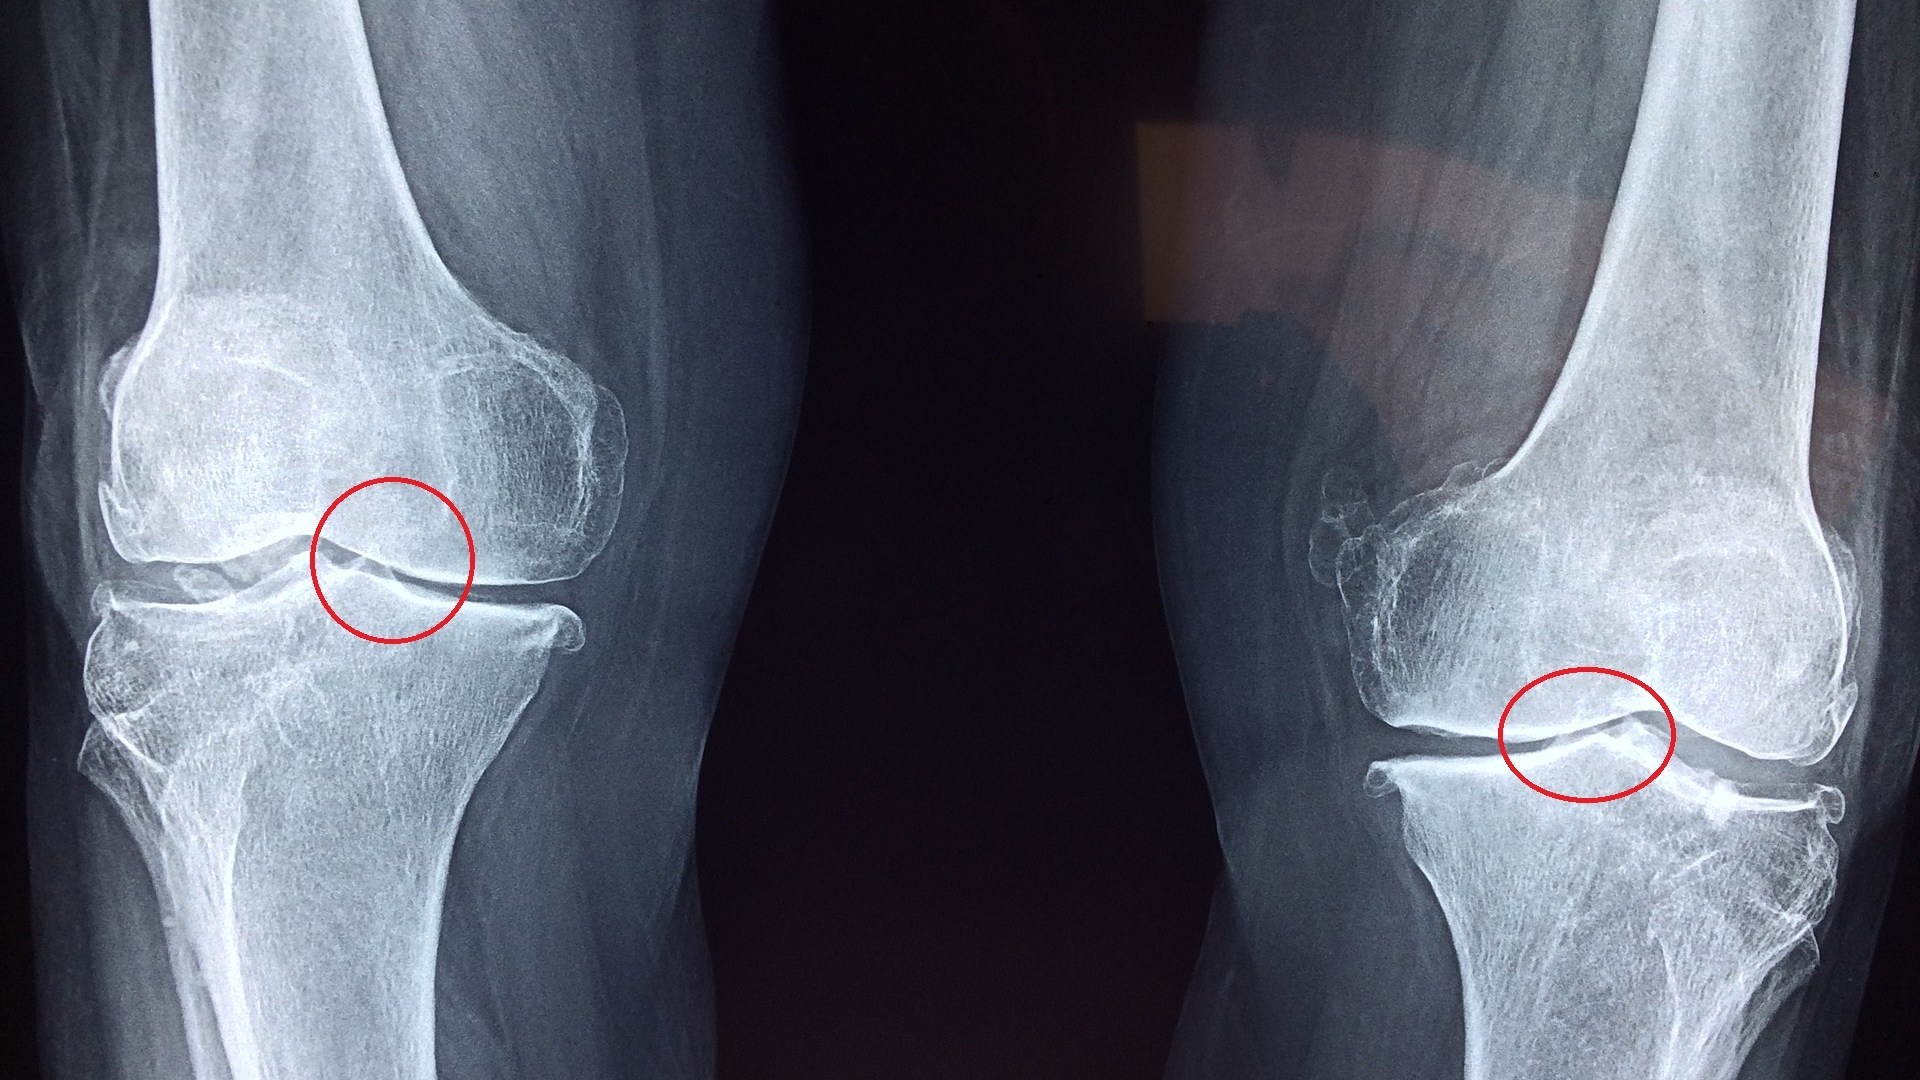

Je dünner und unflexibler die Knorpelschicht (Kreis) wird, desto stärker schreitet die Arthrose fort und desto problematischer werden auch bestehende Haltungsfehlstellungen.

Wenn die Knorpelschicht immer dünner wird, versucht der Körper, gegenzusteuern, indem er neuen Knorpel einlagert. Leider funktioniert das aber nicht „so gut wie neu“: Der hochelastische hyaline Knorpel wird durch wesentlich unflexibleren Faserknorpel ersetzt. Schon das sorgt dafür, dass das Gelenk insgesamt weniger geschmeidig ist. Allerdings ist Faserknorpel auch nicht so belastungsresistent, sodass er noch schneller wieder zerstört wird. Mit fortschreitender Krankheit wird die Knorpelschicht immer dünner. Die Bewegungen werden schwergängiger und schmerzhafter, bis im letzten Stadium der Arthrose Gelenk und Gelenkpfanne direkt aufeinander aufliegen – ein äußerst schmerzhafter Prozess.